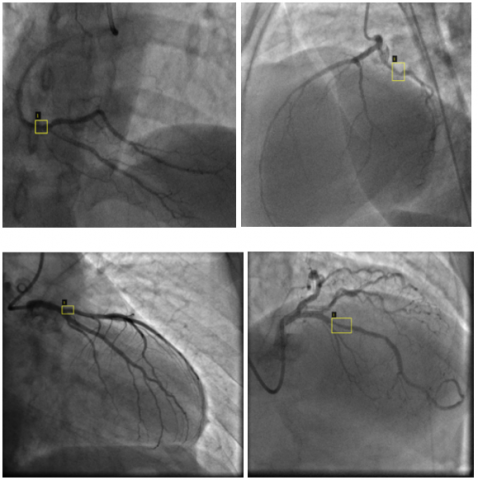

Figure 12 presents sample results from all datasets, showcasing the outputs generated by the YOLO models in the context of vascular occlusion detection. Each entry in the figure includes a representative example of the model’s predictions, illustrating how accurately the models identified and localized the specified targets within the angiographic images. The samples are selected to highlight each model’s performance across different datasets, demonstrating their ability to generalize their learning the images that are not used for training. This figure not only serves to visualize the effectiveness of the detection algorithms but also provides a comparative perspective on how each model performs in identifying occlusions under varying conditions and complexities present in the datasets. By examining these results, we gain insights into the models’ strengths in accurately recognizing vascular blockages, as well as any potential limitations in their detection capabilities.

Figure 12. YOLO Models’ sample predictions for vascular occlusion detection across the datasets

Figure 12 displays representative samples of the predictions made by YOLO v5, v7, and v8 across different datasets. The visual comparisons highlight the models' abilities to accurately identify and localize areas of vascular occlusion. YOLO v5 and YOLO v8 consistently detected stenotic regions with high precision in most samples, particularly in Datasets 1, 2, and 3. However, the performance variability of YOLO v7, especially in Dataset 4, suggests limitations in handling more complex or less distinct features present in certain angiographic images. These results emphasize the differences in model generalization capabilities and the impact of dataset characteristics on detection performance.